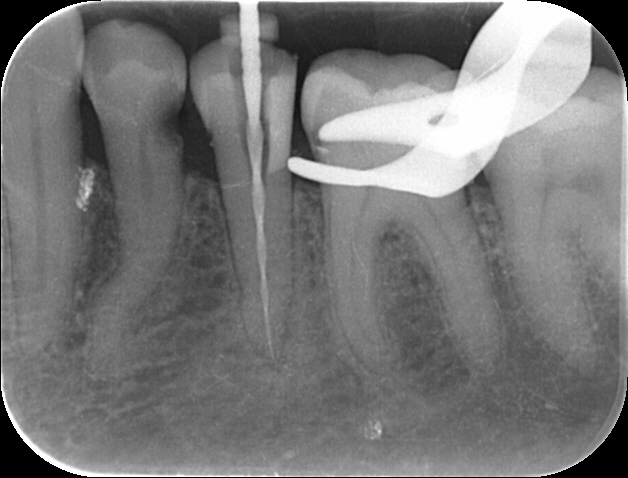

Wenn´s schnell gehen soll…